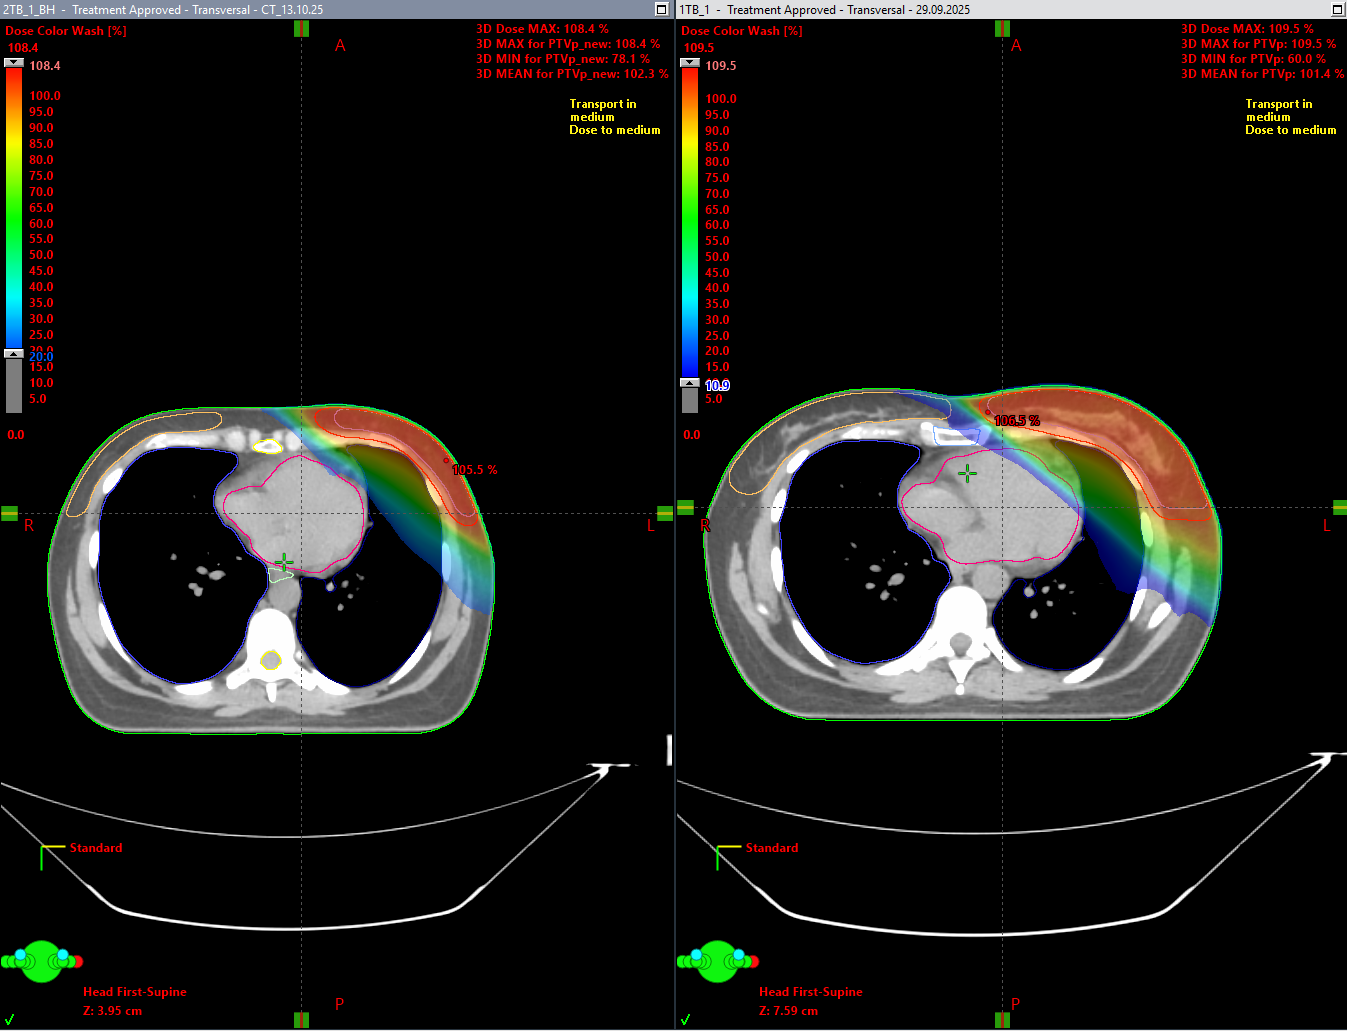

Для оценки эффективности методики в центре был проведён сравнительный анализ на группе пациентов. Каждому из них выполнены два вида КТ-разметки:

- на свободном дыхании;

- с задержкой дыхания (вдох, используемый для синхронизации).

Медицинскими физиками были созданы два варианта планов облучения, основанные на данных обеих разметок. Сравнение показало:

- статистически значимое снижение дозы на сердце при использовании методики дыхательной синхронизации;

- улучшение распределения дозы в зоне интереса без увеличения нагрузки на окружающие ткани.